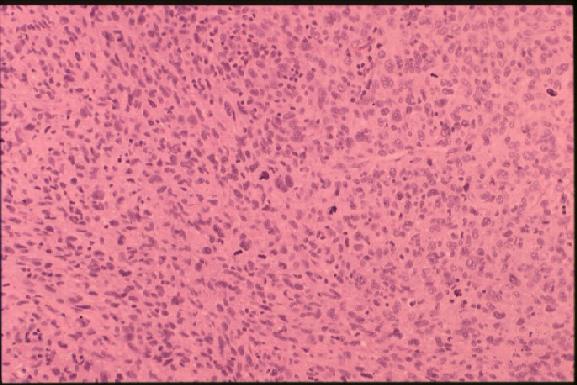

2. The left pleura is firmly adherent to the chest wall, and 330 ml of yellow pleural effusion is present in the left pleural cavity and 400 ml in the right. Pericardial space is firmly adhered. An elastic firm and smooth surfaced tumor is noted around the main trunk of the pulmonary artery (PA) and its main branches that measures about 9 x 6 x 5 cm in external dimension inclusively, accompanying a dumb-bell shaped, apparently separate mass on the posterior aspect of the left atrium that measures 8 x 6 x 3 cm in dimension. Anterior incision through right ventricular outflow tract and pulmonary trunk (jpg.43KB) reveals a tumor thrombus occupying the lumen of the main trunk and bilateral branches of the PA (elastic van Gieson and HE stains [jpg.34KB]), measuring about 7 x 4 x 3 cm in dimension, which in a retrograde fashion protrudes from the outlet at the level of the pulmonary valve into the lumen of the dilated right ventricle that measures 3.5 x 3.5 cm in dimension with smooth surface, and distally involves the upper lobe branch of the right PA 4.0 cm long from the hilus, and the upper and lower lobe branches of the left PA massively. The lumen of the right lower lobe branch of the right PA is free of invasion. The stent, which is consisting of four tandemly and one parallelly arranged metal pieces fairly evenly implanted in the lumen from the pulmonary valve to the hilum of the right PA, is being completely embedded in the tumor thrombus. The lumen of the stent, too, is almost completely obstructed by organizing tumor thrombus. On cut surface at the anterior aspect of the main PA, where the tumor is invading its wall and forming a nodular sessile mass that measures about 6 x 3.5 x 4 cm in dimension, the tumor is yellowish white, solid and uniform. The remaining thread from the previous operation is also identified there. The esophagus and ascending thoracic aorta and other mediastinal structures are free of involvement. Microscopic examination reveals diffuse proliferation of atypical spindle cells arranged in storiform pattern (ordinary type) (jpg.45KB) or diffuse proliferation of pleomorphic giant cells, including bizarre multinucleated giant cells (giant cell type) (jpg.47KB). Immunostains reveal distinct positivity of tumor cells for vimentin (jpg.44KB), questionable positivity for lysozyme, S-100 and alpha-1-anti-trypsin, and negative staining for desmin and SMA.

The histological diagnoses of primary pulmonary artery sarcoma are various, including leiomyosarcoma, rhabdomyosarcoma, fibrosarcoma, myxosarcoma, osteosarcoma, undifferentiated sarcoma, malignant mesenchymoma, etc. One of the two cases reported by Nonomura et al (1988) was diagnosed with malignant fibrous histiocytoma by histologic, immunohistochemical and electron microscopic studies. The histologic, electron microscopic and immunohistochemical features of the current case, too, is consistent with those of malignant fibrous histiocytoma.